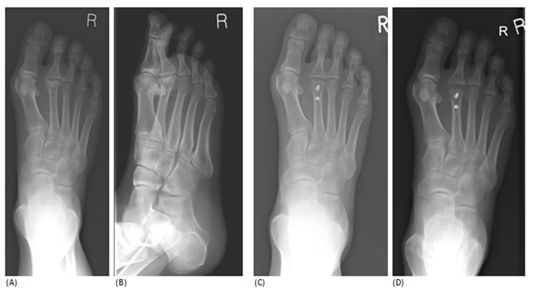

There were 13 female and 2 male patients with a mean age of 36.6 years (range 15-61). The mean follow up period was 15.7 months (range 9-36). 12 patients indicated that the operation provided complete pain relief (p<0.05). 3 patients suffered mild to moderate post-operative pain. 14 patients had disease of the 2nd metatarsal head and 1 patient had disease of the 3rd metatarsal head. X-rays showed an average healing time of 12.7weeks (range 6-24weeks). Patient satisfaction was excellent at an average of 9.3 (range 6-10) (Figure 6). The mean AOFAS scores were 54 pre-operatively and 82 post-operatively. The mean metatarsal head shortening was 2.18mm (range 0.02-5.51). 1 patient developed a haematoma over the wound site within a week of surgery, which resolved spontaneously. No other complications were reported and there was no neurovascular deficit evident in any patients.

Figure 6 Pre-operative radloaraph showtnc marked flattenlna and deformity of the 2• metatarsa l  head with secondary severe deaeneratlon . There Is thlckenlna of the metatarsal shaft; 8,Oblique view showlna these chanaes; C, Immediate post-opera tive radloaraph showina a more anatomical metatarsal  articular surface and screws In situ; o.Final follow-up radloaraph taken at 18 months post-operation . This shows evidence of re-shaplna of the metatarsal head and screws are In situ.